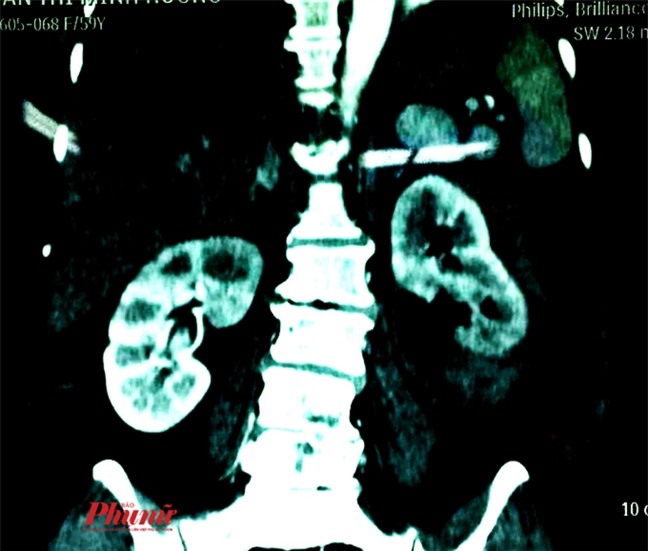

Từ kết quả chụp CT, bác sĩ Nguyễn Đạo Thuấn xác định bệnh nhân bị viêm thận – bể thận sinh hơi giai đoạn 3B (giai đoạn cuối). Quả thận trái của bà H. đã bị sưng phù, to gấp đôi với bình thường.